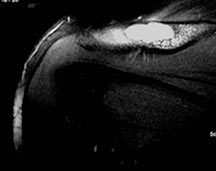

- May arise from any bone and any site within a bone (epiphyseal, metaphyseal, diaphyseal)

- Radiographically variable appearance: may appear benign (geographic) or malignant (permeative or moth eaten)

- Humerus